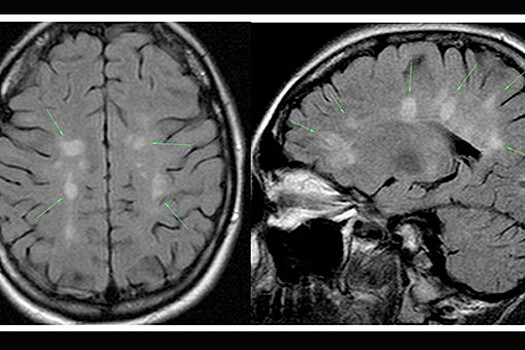

Вопреки сложившемуся стереотипу, рассеянный склероз не имеет отношения к проблемам с памятью у пожилых людей. Это аутоиммунное заболевание, которое характеризуется множественными поражениями миелиновой оболочки нервных волокон головного и спинного мозга, которая необходима для передачи сигналов между нервными клетками.

Для оценки состояния пациента и постановки диагноза неврологи используют шкалу состояния функциональных систем и расширенную шкалу оценки инвалидизации. С помощью первой они оценивают выраженности поражений, с помощью второй — общую степень инвалидности пациента. Также для уточнения диагноза используется магнитно-резонансная томография.